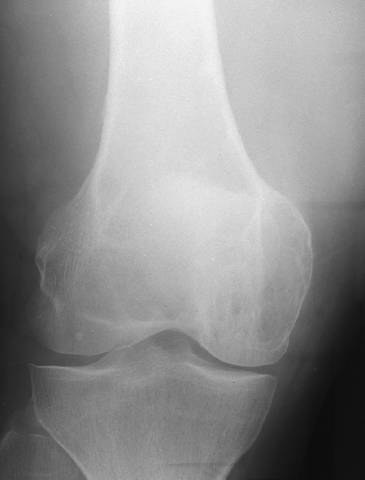

Kuva 1.

Polven jättisolutuumori.

Lobulaarinen, osteolyyttinen, luuta laajentava tuumori. Ääriviiva on yleensä tarkka, mutta ääriviivan skleroosi puuttuu